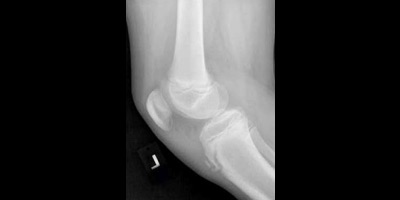

20200319-image